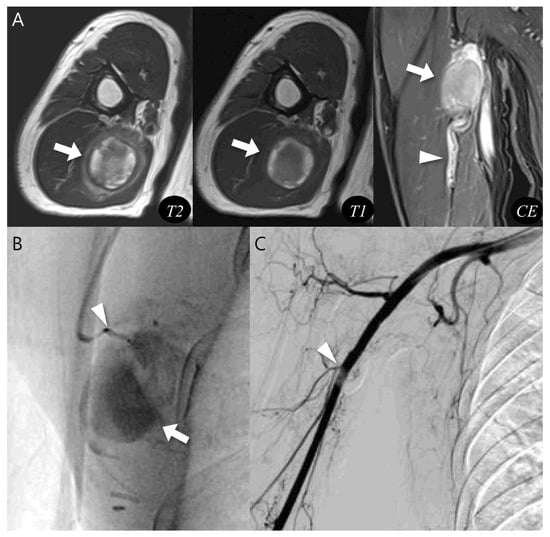

Pseudoaneurysm Versus Chronic Expanding Hematoma on MRI: Hematoma-like Lesions with Distinct Therapeutic Strategies

by

Seul Ki Lee, Jun-Ho Kim and Jee-Young Kim

Biomedicines 2025, 13(11), 2834; https://doi.org/10.3390/biomedicines13112834 - 20 Nov 2025

Background/Objectives: Pseudoaneurysm and chronic expanding hematoma (CEH) are uncommon soft tissue lesions that can mimic hematoma or hemorrhagic tumors on magnetic resonance imaging (MRI). Because treatment strategies differ, accurate differentiation is important. This study aimed to compare MRI characteristics of pseudoaneurysm and CEH

Background/Objectives: Pseudoaneurysm and chronic expanding hematoma (CEH) are uncommon soft tissue lesions that can mimic hematoma or hemorrhagic tumors on magnetic resonance imaging (MRI). Because treatment strategies differ, accurate differentiation is important. This study aimed to compare MRI characteristics of pseudoaneurysm and CEH and identify distinguishing imaging features. Methods: We retrospectively reviewed 12 patients diagnosed between June 2010 and June 2023 with pseudoaneurysm (n = 6) or CEH (n = 6). Patient demographics, lesion depth, and size were compared. MRI features were evaluated for morphology, internal characteristics, pulsatile artifact, and involvement of adjacent structures. Results: Pseudoaneurysms were consistently located in the muscle layer, whereas CEHs were predominantly found in the subcutaneous fat layer (83.3%, p = 0.015). CEHs were significantly larger than pseudoaneurysms (13.5 ± 3.9 cm vs. 6.1 ± 3.3 cm, p = 0.005). Pseudoaneurysm more frequently exhibited ovoid morphology (100%), central flow void on T1WI and T2WI (100%), inner peripheral high SI on T1WI (83.3%), and neurovascular bundle involvement (100%) (all p < 0.05), while CEHs demonstrated multilobular morphology (100%) and internal septations (83.3%) (p < 0.05). Conclusions: Lesion location, size, morphology, central flow void, inner peripheral high T1 signal, septation, and neurovascular involvement enables reliable MRI differentiation between pseudoaneurysm and CEH, guiding accurate diagnosis and guiding appropriate management.